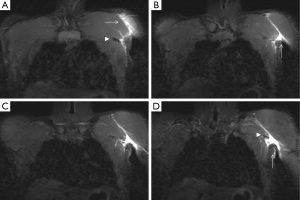

A normal pectoralis major tendon should have uniform low signal intensity on MR imaging. Like US (34), tears of the pectoralis major tendon seen on MR imaging exhibit different degrees of tendon abnormality, depending on the degree of injury. A grade I strain of the muscle belly will have feathery intramuscular fluid-sensitive signal intensity, which represents oedema and/or haemorrhage. Grade II injury will appear as a partial tear with an intramuscular hematoma, while grade III injury has a complete tear with possible retraction (Figures 11-13). As a matter of fact, a partial tear involving only the posterior sternal segments, the anterior clavicular head and tendon will be intact, with the long head of the biceps tendon in place. With complete tears involving both the sternal head and the clavicular head, however, there will be disruption of the entire tendon, with anterior displacement of the long head of the biceps tendon (35).

The rotator cuff stabilizes the humeral head in the glenoid cavity and comprises the supraspinatus, infraspinatus, teres minor and the subscapularis muscles and tendons. They all originate in the scapula (the supraspinatus on the supraspinous fossa, the infraspinatus on the infraspinous process, the teres minor on the posterior surface of the scapula and the subscapularis on the subscapular fossa), and their tendons insert on the humerus (the first three on the greater tubercle of the humerus, and the subscapularis on the lesser tubercle). Tears of the rotator cuff are more common in older patients, generally associated with degenerative changes (the supraspinatus being the most commonly involved). However, acute traumatic tears can also occur in young and athletic individuals. Lesions usually affect the humeral insertion of the rotator cuff tendons, but can also more rarely affect their muscular origins in the scapula. Clinical examination and plain radiographs are almost never helpful in predicting rotator cuff muscle tears immediately after trauma, whereas MRI has proven its usefulness in the assessment of these lesions (Figure 14). Patients with injuries at the muscle origin or belly are treated conservatively (38).